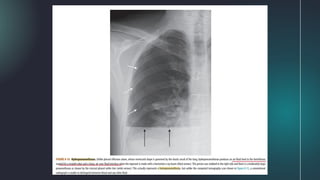

● Pseudotumors (also called vanishing tumors) are sharply

marginated collections of pleural fluid contained either

between the layers of an interlobar pulmonary fissure or in a

subpleural location just beneath the fissure.

● They are transudates that almost always occur in patients

with congestive heart failure.

● Imaging findings of a pseudotumor are characteristic and

should not be mistaken for an actual tumor.

Fissural Pseudotumors